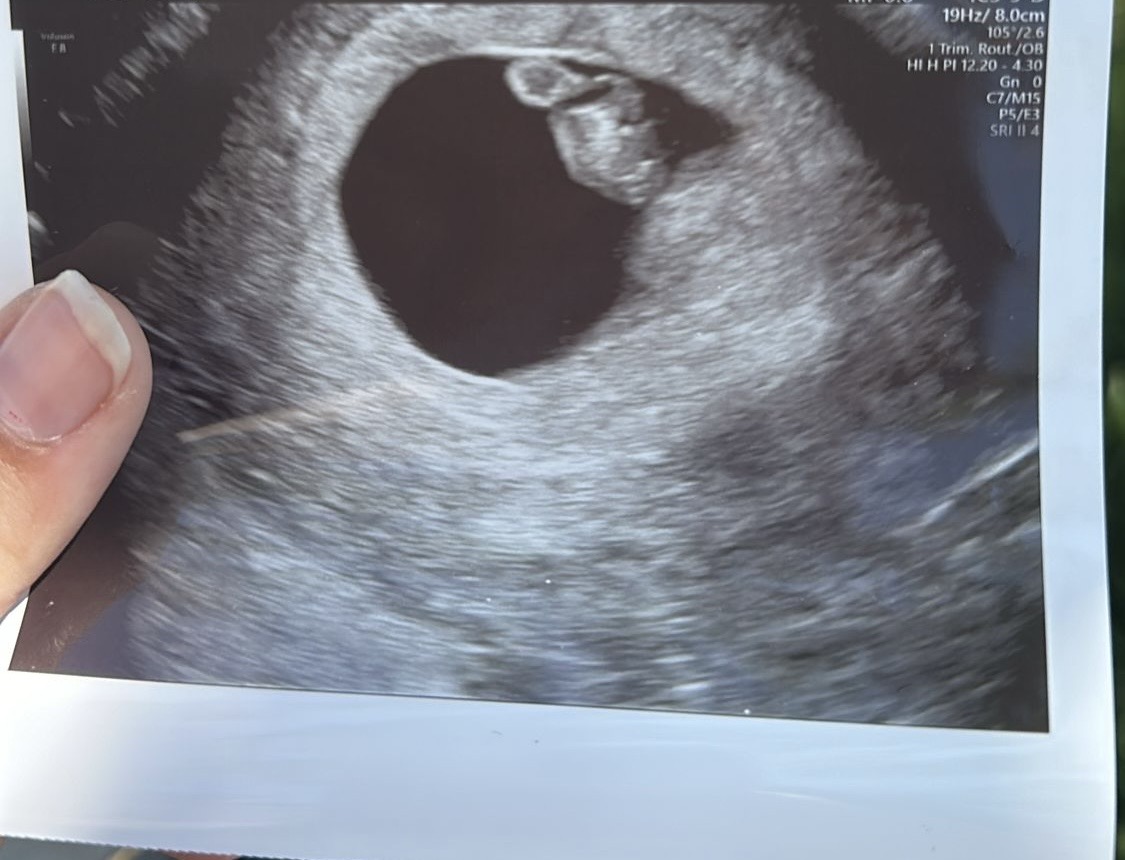

@marcela228 gratulujem, presne si pamätám aká šťastná som si niesla túto fotku.♥️